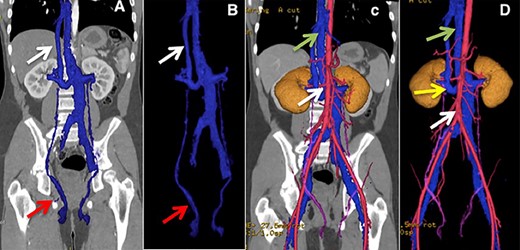

A 73-year-old female patient with no relevant history, upper and lower endoscopies were performed due to dyspepsia, biopsies of an anal lesion reported a neuroendocrine carcinoma, in order to stage the malignancy, CT of the abdomen and pelvis revealed a lymphatic mass in front of the sacrum and presence of an anatomical variant of the left IVC, which continues with the azygos vein to the right of the thoracic spine. (Fig. 3).

(A) Lower arrows show ovarian veins, upper arrow shows hypoplastic suprahepatic segment of the IVC. (B) Lower arrows show ovarian veins, right upper arrow shows hypoplastic suprahepatic segment of the IVC, left upper arrow shows azygos vein. (C and D) Lower arrow shows aorta, upper arrow shows azygos vein.